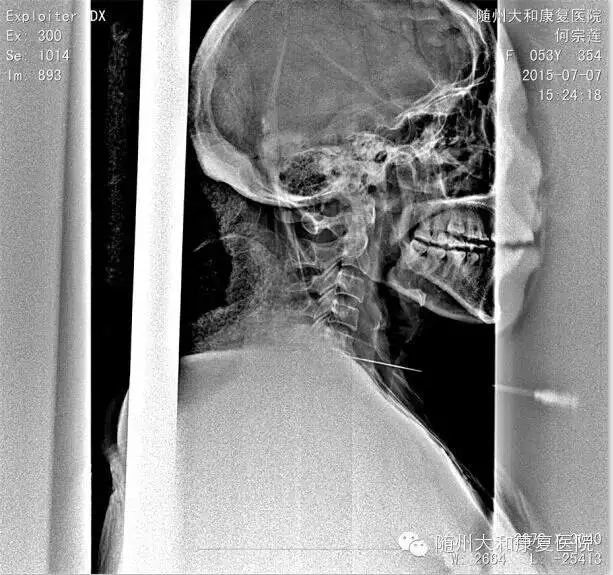

何女士:48岁,曾都区星光村一组居民,有较为严重的颈椎病史,因为平时以卖菜为生,疼痛起来,自己忍忍就过去了,可不想最近症状突然加重,整个右上肢麻木、疼痛难忍才来我院就诊。

经门诊CT检查。我院付主任为何女士诊断为神经根型颈椎病,其中5-6节颈椎间盘突出,右侧椎间孔狭窄,伴右上肢麻木、疼痛等症状。

在经我院杨院长和付主任的分析讨论后,最终决定为何阿姨进行射频消融+臭氧手术进行治疗。手术非常成功,术后,何女士上肢麻木感消失,疼痛减轻,目前正在我院配合做康复理疗。